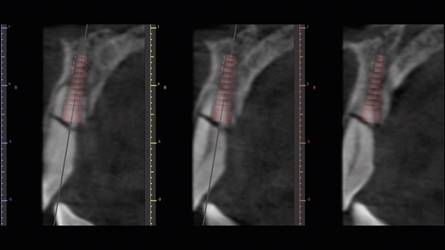

Posteriormente se realizó una impresión de alginato y vaciado en yeso del maxilar, se eliminaron mecánicamente ambos incisivos centrales. Este modelo se digitalizó con un escáner extraoral (3Shape, Trios) y se obtuvo un archivo STL. Luego con esto datos se hizo una coincidencia digital entre el CBCT y el archivo STL, utilizando el software BlueSky plan, (BlueSky bio). Se planificaron dos implantes cónicos de conexión interna de 3.8 x12 mm (Biohorizons), separados de la parte vestibular de las raíces y asegurando su correcto posicionamiento implantario (Img 1). Luego se diseñó una guía quirúrgica en el mismo software, exportada e impresa en ácido poliláctico (PLA) por una impresora de tecnología de deposición de material fundido (FDM) (Duplicator 7, Wanhao, China). Después de la anestesia local, se extrajo la porción coronal de ambos dientes fracturados, luego las partes apicales restantes se dividieron mesio-distalmente con una fresa de diamante de alta velocidad dejando dos porciones. Se retiró la parte palatina y se conservaron 5 mm de la pared vestibular radicular, posteriormente se instaló la guía quirúrgica en posición (Fig 2 y 3).

El protocolo de fresado llegó a los 21 mm de profundidad y a la fresa de 3.2 mm de diámetro. Ambos implantes alcanzaron 40 N de torque, todo bajo un protocolo de cirugía e inserción guiada estricta de implantes (Fig. 4).